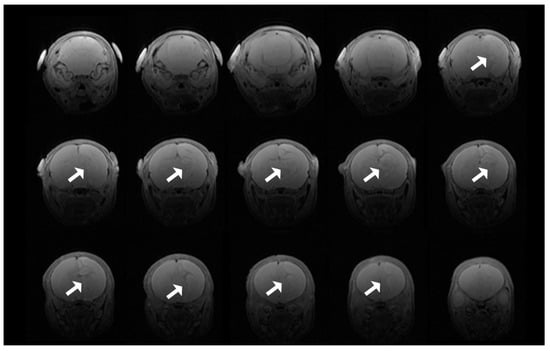

T2 images demonstrated hyperacute infarction in four animals after hypothermia treatment, two in each of the VEH and NVD groups (Figure 7) within 2 h of hypoxia, which usually evolves over 24 h [].

Figure 7.

T2 scan showing progression of infarction for an animal from the VEH group. Of note, the right hemisphere is on the left side of the magnetic resonance imaging (MRI) images.